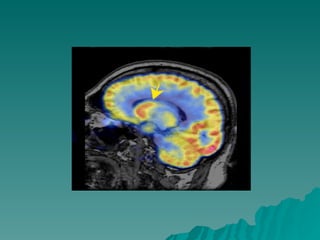

Corpo do caudado Corte Sagital

Corpo do caudado Corte Coronal